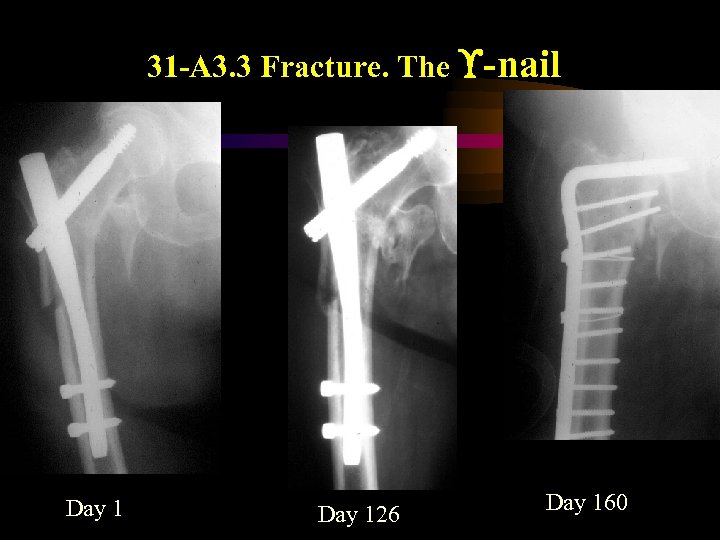

31 -A 3. 3 Fracture. The -nail Day 126 Day 160

31 -A 3. 3 Fracture. The -nail Day 126 Day 160